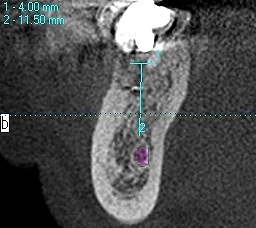

インプラントのCTを用いた術前診断 右下の歯が破折により将来をにらんで今の年齢でインプラントにしておきたい|お知らせ |広島市安佐南区の歯科医院 インプラントのCTを用いた術前診断 右下の歯が破折により将来をにらんで今の年齢でインプラントにしておきたい トップ お知らせ・ブログ お知らせ インプラントのCTを用いた術前診断 右下の歯が破折により将来をにらんで今の年齢でインプラントにしておきたい インプラントのCTを用いた術前診断 右下の歯が破折により将来をにらんで今の年齢でインプラントにしておきたい 術前パノラマになります 歯が破折 インプラント埋入後になります 機能時のデンタルレントゲンになります 右下の7番部の術前術後のCTになります 右下の6番部の術前術後のCTになります 4mmの13mmというインプラントを埋入 Web診療予約 初めての方へ 選ばれ続ける理由 院内設備について 歯が痛いしみる一般歯科 歯がぐらぐらする歯周病 健康な歯を保ちたい予防歯科 子供の虫歯予防をしたい小児歯科 銀歯をセラミックに審美歯科 白い歯を目指しませんか?ホワイトニング 矯正専門医がいるので安心矯正歯科 抜けた歯を補いたいインプラント・入れ歯 医院案内 スタッフ紹介 メリィハウス歯科クリニックオフィシャルホームページ ラベンダー歯科クリニックオフィシャルホームページ お知らせ・ブログ ホーム 診療科目 一般歯科 歯周病治療 予防治療 小児歯科 審美治療 ホワイトニング 矯正歯科 入れ歯・インプラント マウスピース矯正 初めての方へ 院長・スタッフ 設備紹介 医院案内・アクセス メニューを閉じる